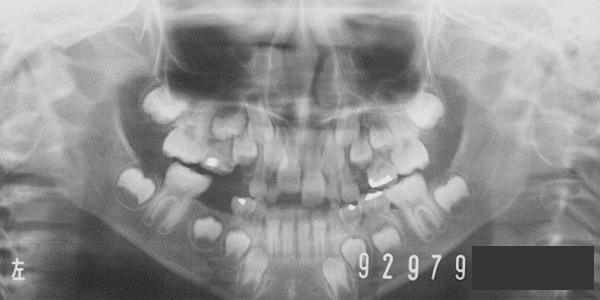

4 Initial Visit 8-29-’79

Although there were many missing deciduous teeth, the number of permanent teeth was not problematic (4). The amount of negative overjet was significant (1). On cephalometric radiographs, the mandibular ramus was not relatively long, but the large gonial angle and the long mandibular body were noticeable, indicating an overall tendency of the mandible to project inferiorly and anteriorly. High lower facial height was also characteristic.

A potential predisposition to mandibular protrusion was clearly evident.